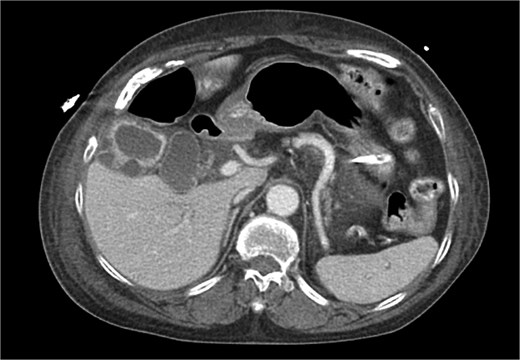

CT chest abdomen pelvis with IV contrast axial view. Gallbladder wall hyperenhancement and multiple intramural hyperattenuating nodes are again apparent in axial imaging.

XGC is typically diagnosed through imaging and histopathological examination. In this case, computed tomography (CT) revealed findings consistent with XGC, including gallbladder thickening and inflammatory changes [3]. However, definitive diagnosis was confirmed by blood cultures and the clinical course. The overlapping features with cholecystitis and biliary tract malignancies pose diagnostic challenges, particularly in acutely ill patients. In transplant recipients, where symptoms may be atypical and infection progresses rapidly, clinical suspicion and early intervention are paramount.